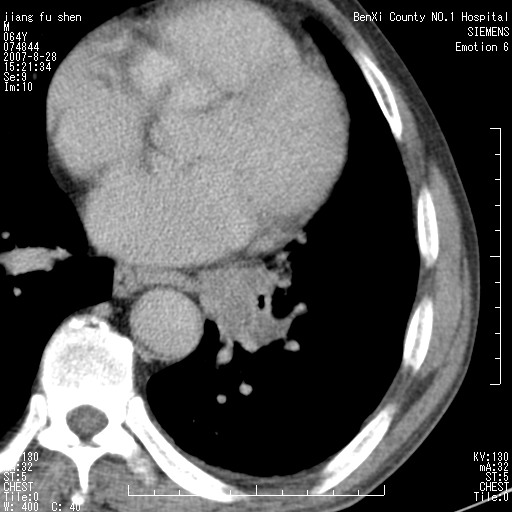

男、64、咳嗽、发烧一周、左肺呼吸音稍弱。既往肺结核,右手结核。

本次扫描患者未带原片,左肺下叶发现病灶。左肺上叶空洞,5组淋巴结肿大,1cm左右。

考虑左肺中央型肺癌并阻塞性肺炎

支持左侧中央型肺癌伴阻塞性肺炎

左肺下叶中央型肺癌